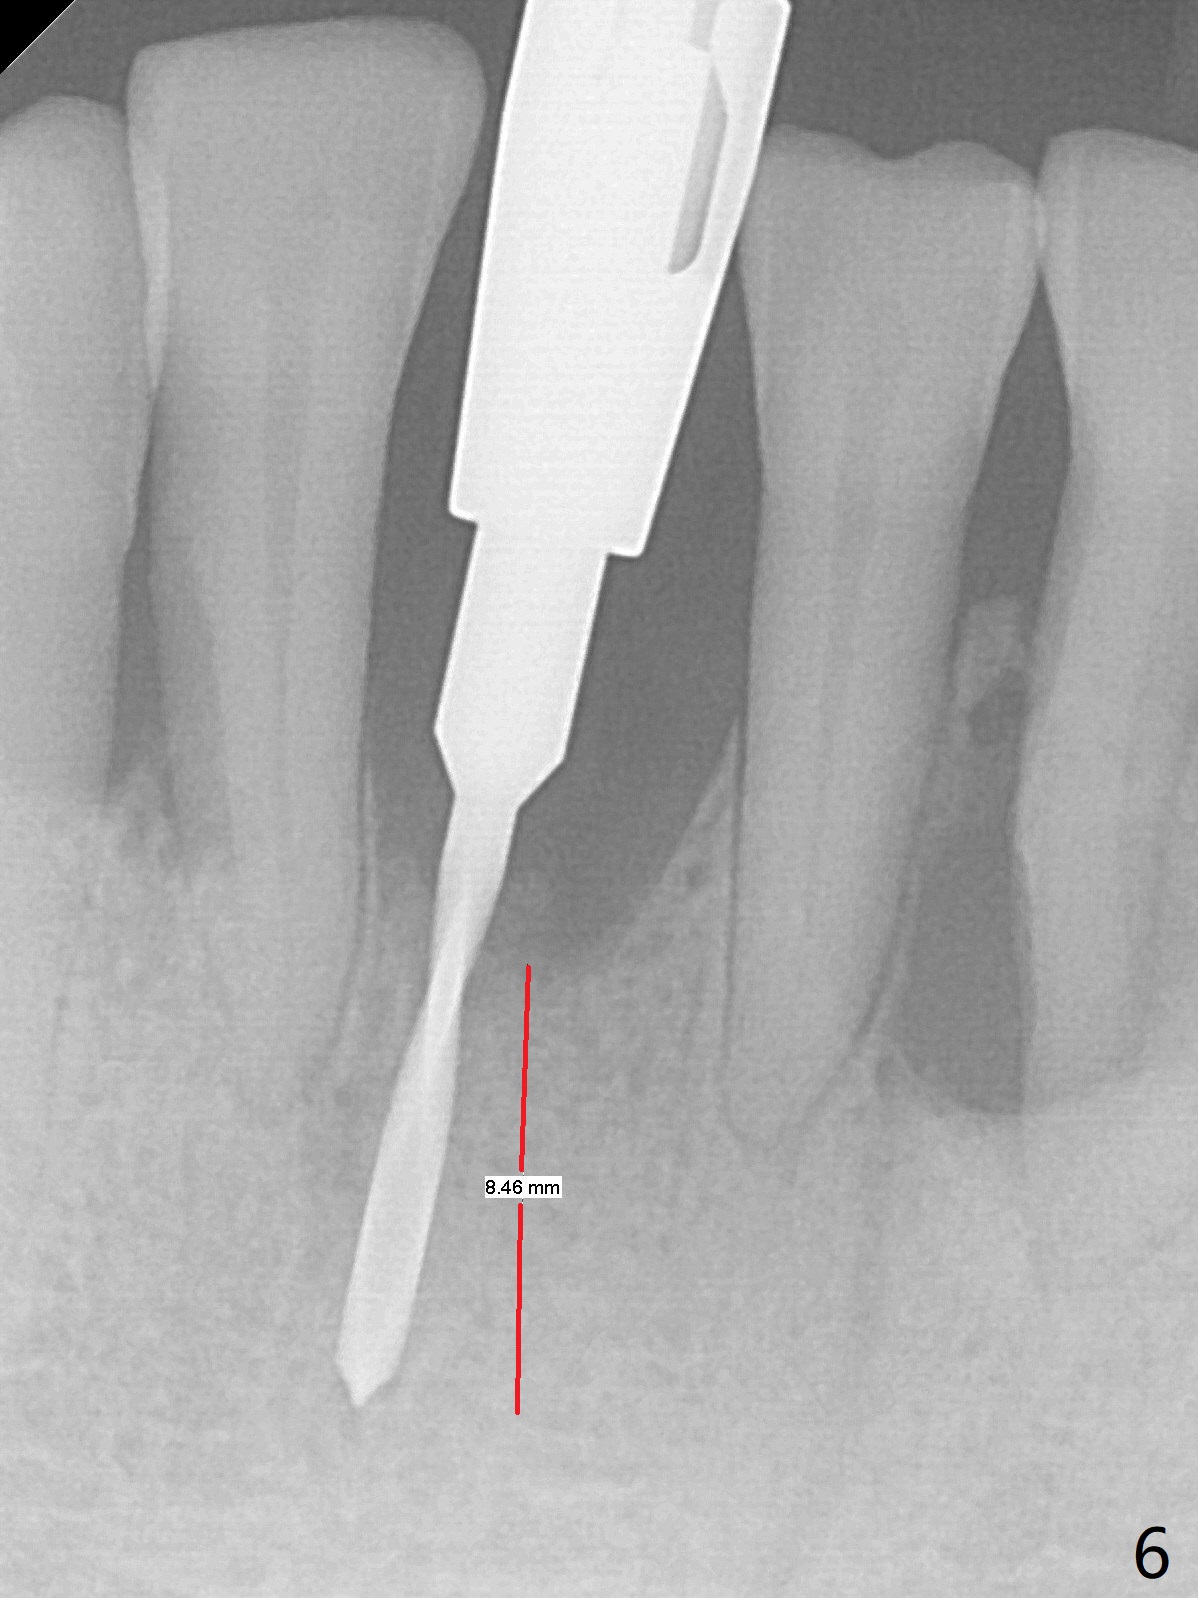

There is gingival inflammation at #25 buccally (Fig.1) and lingually (Fig.2). The bone loss is severe (Fig.3). Soft and hard tissue heights are 5 mm (cuff will be 4 mm) and 10 mm (implant will be 12 mm with 2 mm outside the native bone, Fig.4). The apex of the affected tooth appears deviated distal (Fig.5 *). The initial osteotomy happens to follow the long axis of the socket (Fig.6); to establish a correct trajectory, a new osteotomy should be made at the site labeled as a red line. In fact it is executed as planned (Fig.7). Because of the narrow flat ridge buccolingually, a 2.5x12(4) mm 1-piece implant is placed with >40 Ncm (Fig.8). With deeper placement of the implant, Vanilla graft is placed in 2 steps (Fig.9,10). The patient will return 2.5 months for extraction and implant of the fused teeth #22 and 23. No implant threads are exposed 10 months postop (Fig.11). CT taken 11 months postop shows that the 2.5 mm implant is in the middle of the bone (Fig.12) or 2 years post cementation (Fig.13).